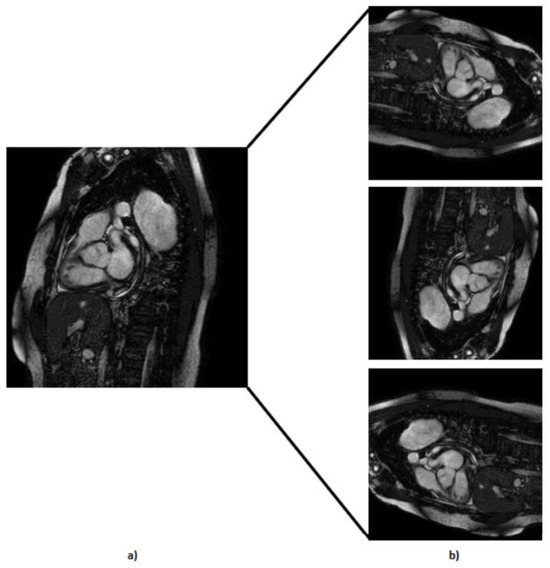

- We used rotational augmentation to rotate photos at 90-, 180-, and 270-degree angles, depicted in Figure 4. This geometric modification not only increased the size of our dataset by 3 times but also created useful variations in orientation, increasing the information available to our models. We only intended to spin the MRIs at four angles because rotating an MRI to a random degree between those mentioned above would not be realistic because the patient is not in a 15 degree position during the exam, for example. This creates 606 new MRIs out of the original dataset.